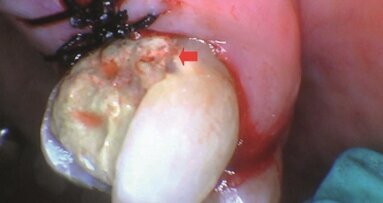

61-letnia pacjentka została skierowana do kliniki z powodu 2 zmian o charakterze uszypułowanego guzka na błonie śluzowej dna jamy ustnej zlokalizowanych pomiędzy ujściami ślinianek podżuchwowych i częścią zębodołową żuchwy. Guzek powstał najprawdopodobniej z powodu złego dopasowania, zbyt długo używanej protezy dolnej. Pacjentka po zakończonym leczeniu onkologicznym 9 lat temu, leczona z powodu nadciśnienia, niepaląca.

Po pomiarze ciśnienia w ambulatorium zakwalifikowano pacjentkę do zabiegu. Przed zabiegiem pacjentka przepłukała jamę ustną roztworem Octeniseptu. Po znieczuleniu nasiękowym: 1 ampułka 2% lidokainy, wykonano zabieg laserem diodowym – długość fali: 980 nm, mocy: 5,5 W, tryb pracy: impulsowy. Zmianę wycięto w całości. Podczas zabiegu uzyskano hemostazę, materiał wysłano do badania histopatologicznego – rokowania dobre.

Kontrola po 4 tygodniach: w okresie pozabiegowym brak powikłań, pacjentka zgłasza lekki ból trwający przez ok. 3 dni po zabiegu, rana na błonie śluzowej dna jamy ustnej całkowicie zagojona, prawidłowy wypływ śliny przez ujścia ślinianek podżuchwowych. Rozpoznanie histopatologiczne: „2 fragmenty tkankowe 0,8 x 0,6 x 0,6 cm i 1,2 x 1 x 0,4 cm pokryte błoną śluzową. Polipy włókniste.